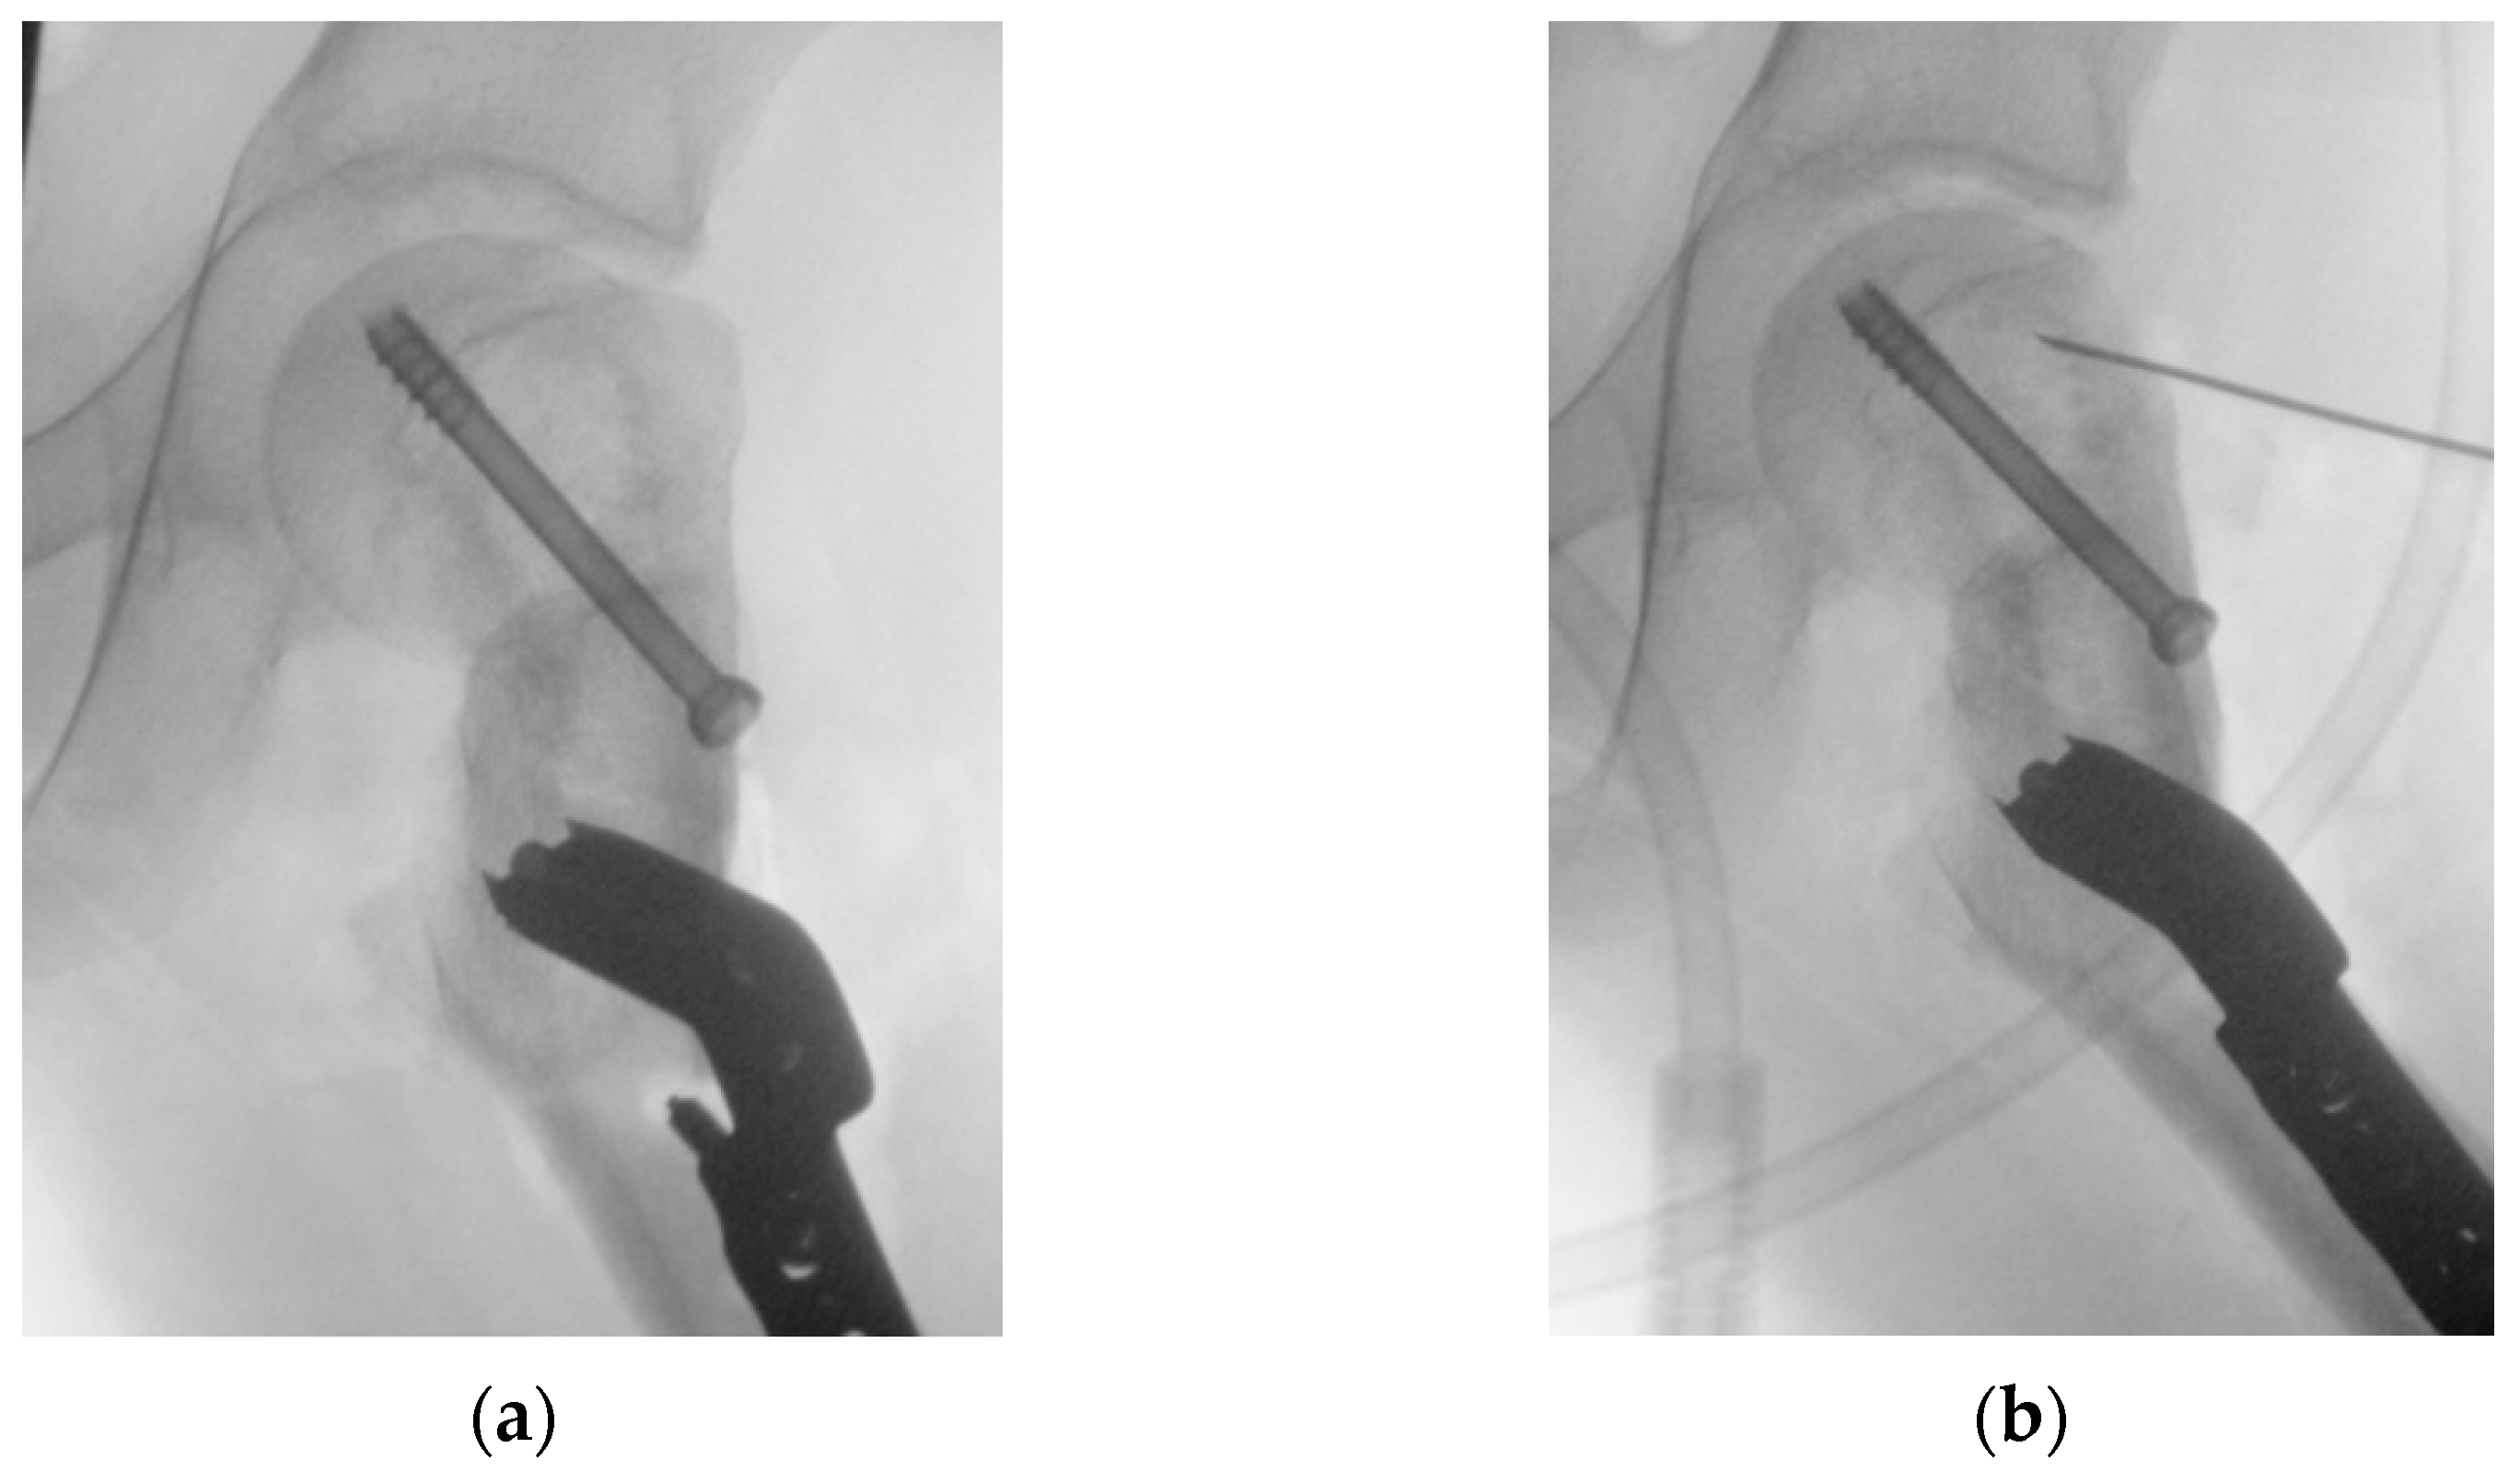

2.4. Results